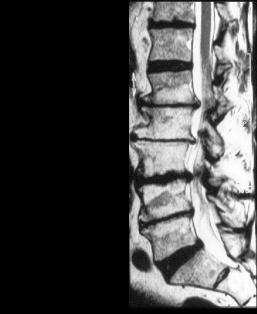

Synonyme: MRT, Magnet-Resonanz-Tomographie, "große Röhre"

Diagnostische Technik zur Darstellung der inneren Organe und Gewebe mit Hilfe von Magnetfeldern. Röntgenstrahlen kommen nicht zum Einsatz. Besonders geeignet ist die Technik zur Darstellung von Nerven- und Bandscheibengeweben. Damit ist sie die bevorzugte Untersuchung bei Wirbelsäulenerkrankungen.

Die MRT beruht nicht auf Röntgentechnik, sondern benutzt das unterschiedliche Rotationsverhalten von Atomen in einem Magnetfeld als Prinzip zur Bildherstellung.

Unterschiedliche Gewebe können mit sehr hoher Detailerkennbarkeit dargestellt werden.

Wichtig: Teilen Sie dem Arzt mit, ob sich Metallteile oder Schrittmacher in Ihrem Körper befinden und ob Sie unter Platzangst leiden.